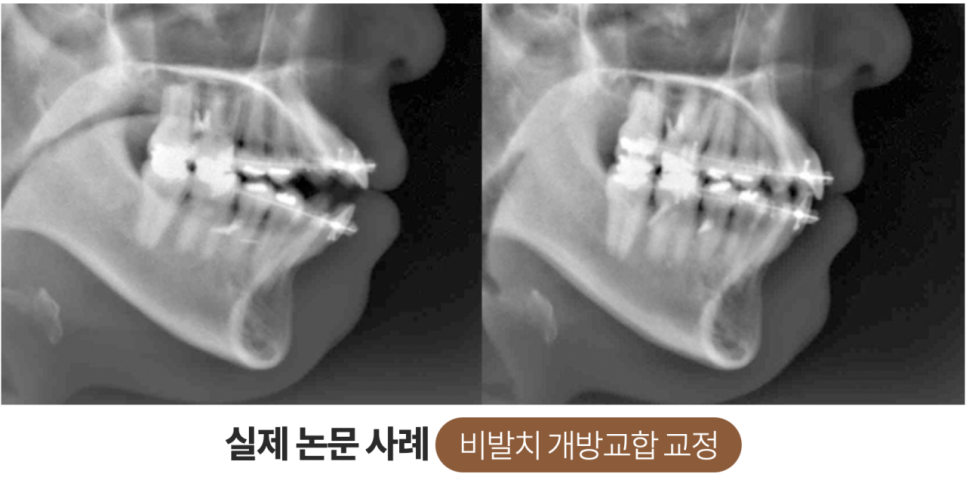

부정교합으로 인해 치아가 맞물리지 않는 상태

사례자분의 경우 상악의 앞니가

심하게 앞으로 돌출된 형태를 띠고

있었으며 상, 하악의 치아가 거의

맞물리지 않을 정도로 심각한

부정교합이 있는 상태였습니다.

부정교합이 개선된 모습

위 사진을 보시면 교정 전 모습과 달리

앞으로 심하게 돌출됐었던 상악의 치아들이

후방으로 이동 후 가지런히 정돈되어

하악 영구치와 교합이 잘 맞물리는 것을

쉽게 확인하실 수 있는데요.